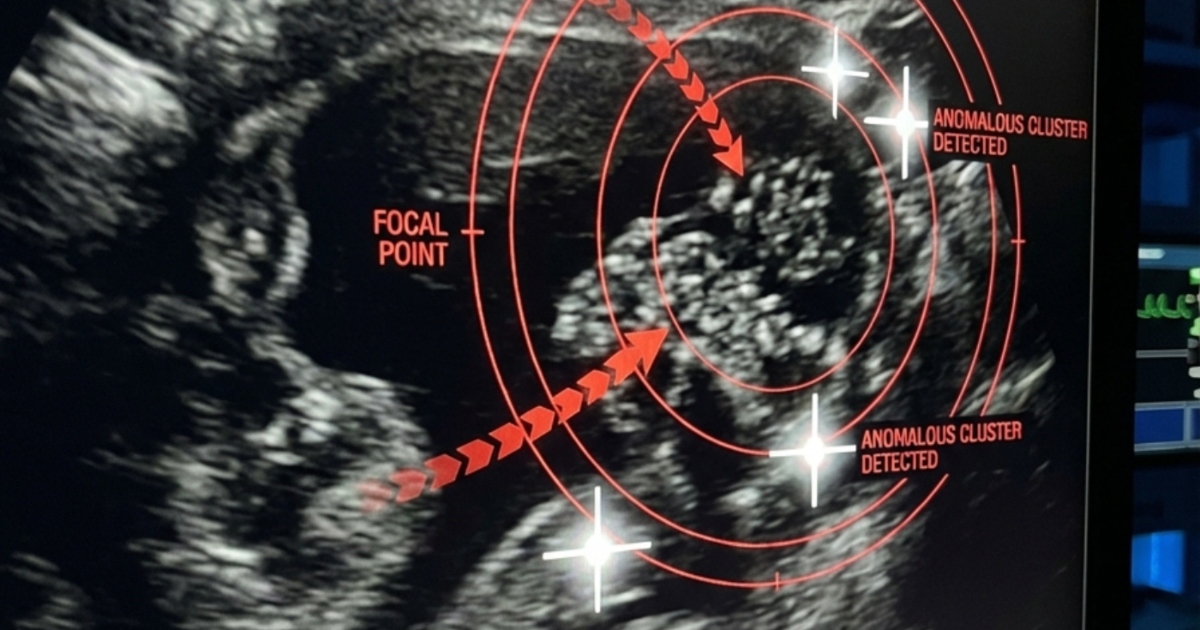

In de gangen van de spoedeisende hulp leek de tijd stil te staan. Terwijl mijn dochter op de brancard kronkelde van de pijn, wachtten we onder bezorgde blikken van de dokters op de resultaten van de echo. Eindelijk kwam de arts naar ons toe en sprak de woorden die geen ouder ooit wil horen: “Een spoedoperatie is nodig.” Wat we dachten dat rugpijn door haar tas kwam, bleek stilletjes een niersteen te zijn die gegroeid was. De steen was verschoven en in de urineleider terechtgekomen, waardoor hevige pijn en een levensgevaarlijke situatie ontstonden.